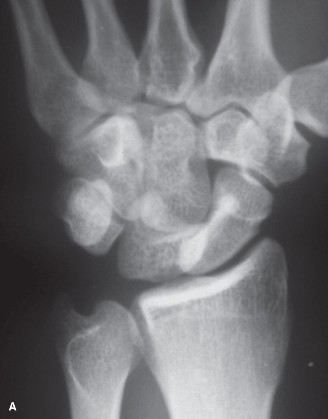

Use 1-2ICSRA to revascularize the scaphoid? CASE 3 ### A patient is brought into the emergency room following a motor vehicle accident. He complains of severe pain in his wrist. Physical examination reveals a tender and swollen wrist. X-rays (Figs. 3–5A–B) are as follows. What is your diagnosis?

Figure 3–5 A–B. (©) Sunil Thirkannad and Christine M. Kleinert.

The correct answer is (D). This x-ray reveals a perilunate injury of the wrist. It is important to be aware of the various radiological parameters that reveal disruption of carpal alignment. Literature suggests that a perilunate injury is missed as much as 25% to 40% of the times. Which radiological signs of perilunate injury can be seen on the above Figs. 3–5A–B .

The correct answer is (E). All three radiological signs are seen on this x-ray. Triangle sign refers to the shape of the lunate seen on the PA view. A normal, well located lunate looks like a tilted trapezium. A triangular-shaped lunate suggests that it is in a hyperflexed position. In the lateral view, a subluxated and volar-tilted lunate has the appearance of a “spilt teacup.” In the above x-ray, Gilula’s first and second lines are broken.